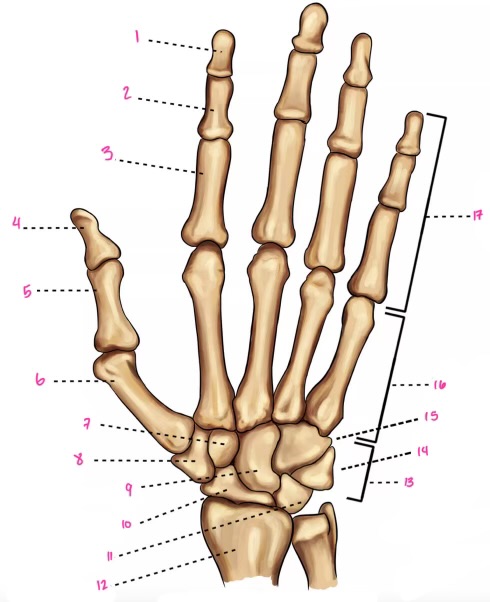

1

1

Hamate

2

New cards

2

Capitate

3

New cards

3

pisiform

4

New cards

9

Trapezoid

5

New cards

10

Trapezium

6

New cards

11

Scaphoid

7

New cards

14

Lunate

8

New cards

15

Triquetrum

9

New cards

16

Pisiform

10

New cards

17

Capitate

11

New cards

18

Hamate

1

Distal interphalangeal

13

New cards

2

Proximal Interphalangeal

14

New cards

3

Metacarpophalangeal

15

New cards

4

Intercapals

16

New cards

5

Distal radioulnar

17

New cards

6

Radiocarpal

18

New cards

7

Carpometacarpals

19

New cards

8

Metacarpophalangeal

20

New cards

9

Interphalangeal

7

Trapezoid

22

New cards

8

Trapzium

23

New cards

9

Capitate

24

New cards

10

Scaphoid

25

New cards

11

Lunate

26

New cards

13

Carpus

27

New cards

14

Triquetrul

28

New cards

15

Hamate

29

New cards

16

Metacarpus

30

New cards

17

Phalanxes